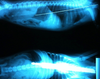

For the past 8 years, Veterinary Practice News has had an annual x-ray contest for the craziest things pet's have eaten. Here are the winners for 2013.